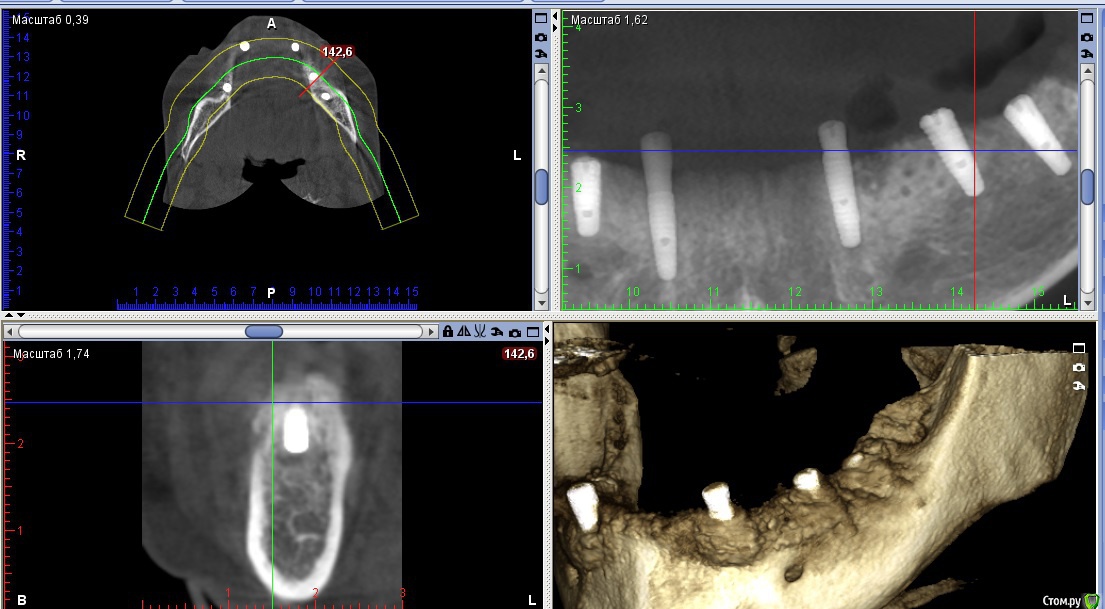

Nitrino1 Опубликовано 21 февраля, 2018 Автор Поделиться Опубликовано 21 февраля, 2018 Коллеги, сделали КТ, картина следующая. Вопрос, как рекомендуете, переустановить на то же самое место только глубже или же все таки менять место?ССТ все таки рекомендуете сделать:? Ссылка на комментарий

dok1 Опубликовано 22 февраля, 2018 Поделиться Опубликовано 22 февраля, 2018 Я бы в таких случаях расщеплялся и заглублялся. И импланты не толще 3.5 мм. Потом после интеграции "шашлычок". Ссылка на комментарий